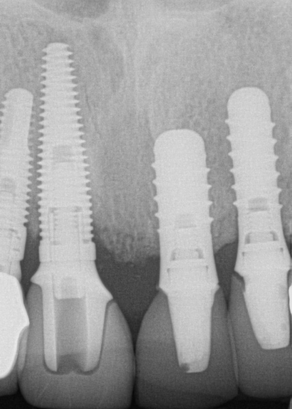

The next case follows the digital protocol for fully guided surgery and prosthetics. A CBCT radiograph, digital impression, and digital photography were the cornerstones to the success of this case. The 3D data set was electronically delivered to the dental laboratory. The data were merged and the process to develop the plan was initiated. The use of CBCT was essential in this case, particularly due to minimal space for placement of individual implants and single-unit crowns. The patient's chief concern was that she wanted to have single-unit crowns instead of fixed crown-and-bridge restorations because she was worried that she would someday find herself in an assisted-living facility; if that were to happen, she wondered, who would help floss under her bridge work? Her decision was to have single implants with individual crowns. CBCT technology is much more accurate in evaluating space maintenance and management.10 Periapicals in the past were rather close for calculating spacing; however, the CBCT identifies the buccal-lingual dimensions as well as the mesial-distal measurements. On review of the completed proposals for implant placement and provisionals, it was determined that there was sufficient spacing for implant placement to allow appropriate emergence profiles for the provisionals and then eventually the final single-unit cemented crowns. The proposal was accepted, and a 3D-printed surgical stent was fabricated, along with the PMMA provisionals (Figure 29 through Figure 35).

Fig 30. Preoperative periapical radiograph.

Figure 30